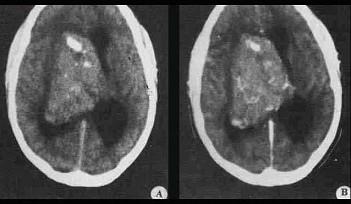

问题 关于畸胎瘤(如图所示)的描述不正确的是()

选项 A.CT值可低度于脑脊液,也可高至接近骨质 B.良性畸胎瘤境界清楚,有完整包膜 C.通常由2~3个胚层来源的组织构成 D.导致性发育迟缓 E.出现未成熟组织意味恶性程度高

答案 E